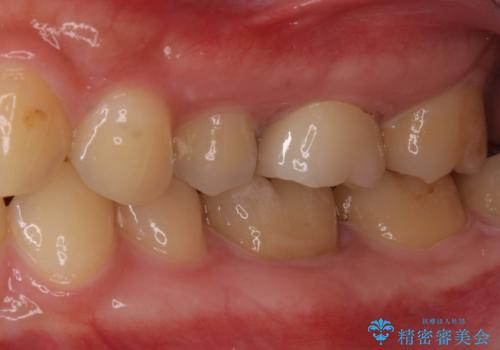

- 奥歯の虫歯と銀歯を気にして来院された患者様です。

セラミックインレーおよびセラミッククラウンによる治療を希望されましたが、虫歯となっている歯は神経近くにまで蝕まれていたため、長期的な予後を鑑みて、PGAインレー(プラチナゴールドインレー)にて修復することとしました。

ゴールドインレーを装着するまでは、金属色が目立ってしまうのではないかと心配されていましたが、表からは見えない位置にあること、銀歯と異なり目立つ色ではないことから、審美的な問題はありませんでした。